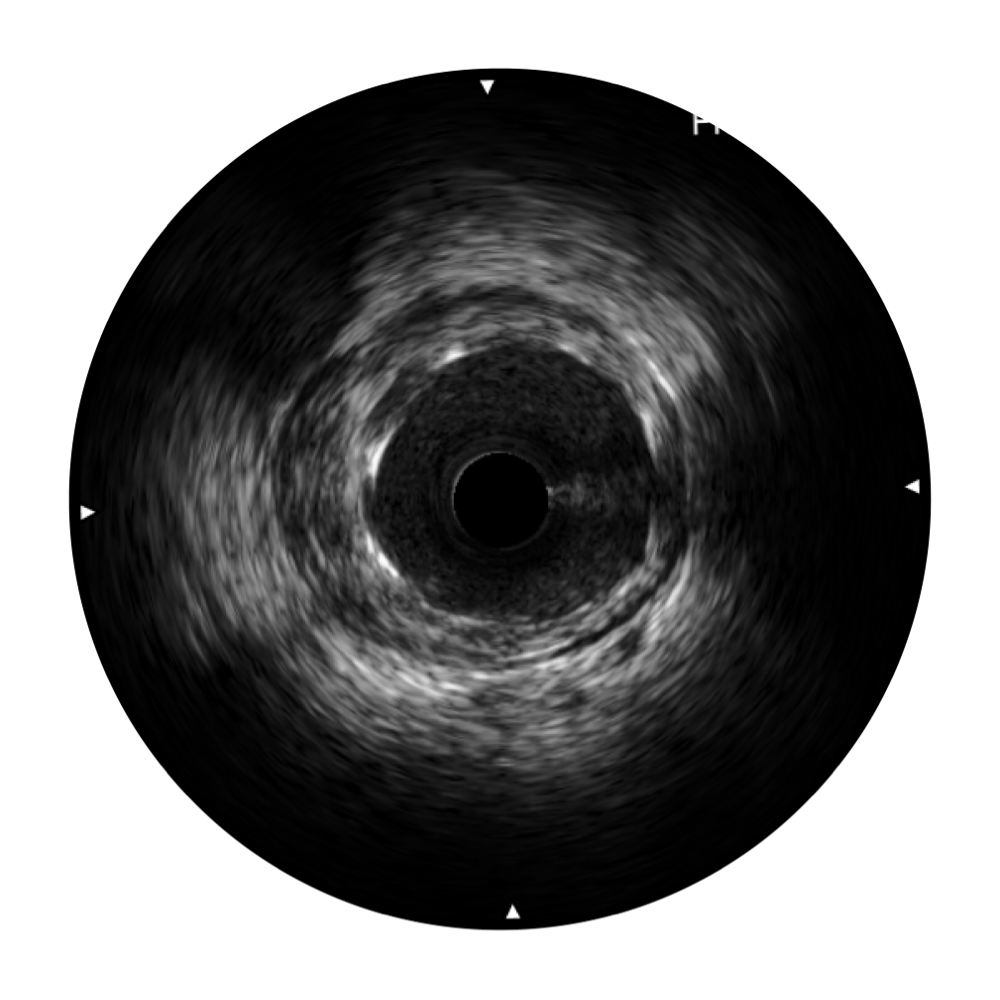

• 传统IVUS图像

对比传统IVUS导管成像,诸侯快讯官网宽频IVUS图像的近场支架梁显影更细腻,远场中膜外血管仍清晰可辨,兼顾远中近,兼顾分辨力与穿透深度